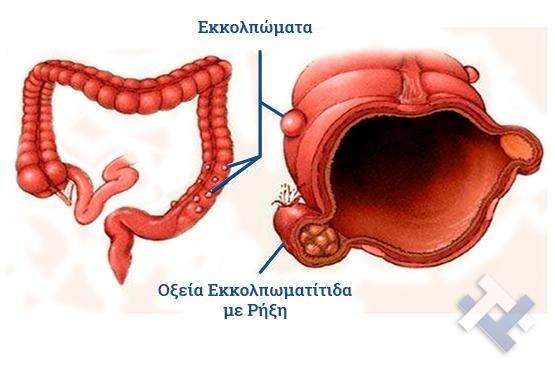

Ο Γενικός Χειρουργός Λιάγκος Γεώργιος MD PhD εκτελεί τις επεμβάσεις Λαπαροσκοπικά, Ενδοσκοπικά, Ανοιχτά Ελάχιστα Επεμβατικά και με Laser. Η θεραπεία εξατομικεύεται σε κάθε ασθενή ανάλογα με τις ανάγκες του. Αναλαμβάνει περιπτώσεις όπως κήλες και κοιλιοκήλες (αντιμετώπιση βουβωνοκήλης, αντιμετώπιση ομφαλοκήλης, θεραπεία επιγαστρικής κήλης, κήλη των αθλητών (Σύνδρομο κοιλιακών προσαγωγών), αντιμετώπιση μετεγχειρητικής κήλης, θεραπεία Μηροκήλης), πέτρες στη χοληδόχο κύστη, λαπαροσκοπική χολοκυστεκτομή, αντιμετώπιση Κύστη Κόκκυγος με λέιζερ (laser), παθήσεις πρωκτού, χειρουργική laser σύγχρονων κυκλικών ινών (αιμορροΐδες αντιμετώπιση, θεραπεία αιμορροϊδων με laser (LHP), αφαίρεση αιμορροΐδων με υπερήχους (HALL-RAR), χωρίς Χειρουργείο με ελαστικούς δακτυλίους (Τεχνική BARON-RBL), θεραπεία ραγάδας πρωκτού (Ραγάδα δακτυλίου), θεραπεία περιεδρικού συριγγίου, θεραπεία περιεδρικού αποστήματος, κονδυλώματα πρωκτού Θεραπεία, δερματικό ράκος (Skin tag) εκτομή, αντιμετώπιση Kνησμού, καρκίνος πρωκτού θεραπεία), παθήσεις Δέρματος, χειρουργική με laser CO2, αφαίρεση μορφωμάτων δέρματος - βιοψίες, αφαίρεση ελιάς (Σπίλου), σμηγματογόνος κύστης θεραπεία, αφαίρεση λιπώματος, είσφρυση όνυχος χειρουργείο, καρκίνος δέρματος θεραπεία, οξεία σκωληκοειδίτιδα, παθήσεις Λεπτού και Παχέος Εντέρου, ειλεός λεπτού εντέρου, εκκολπωμάτωση (Εκκολπωματίτιδα) σιγμοειδούς, καρκίνος παχέος εντέου, κολοστομίες, port χημειοθεραπείας κ.α. εξυπηρετώντας Παγκράτι και γύρω περιοχές.